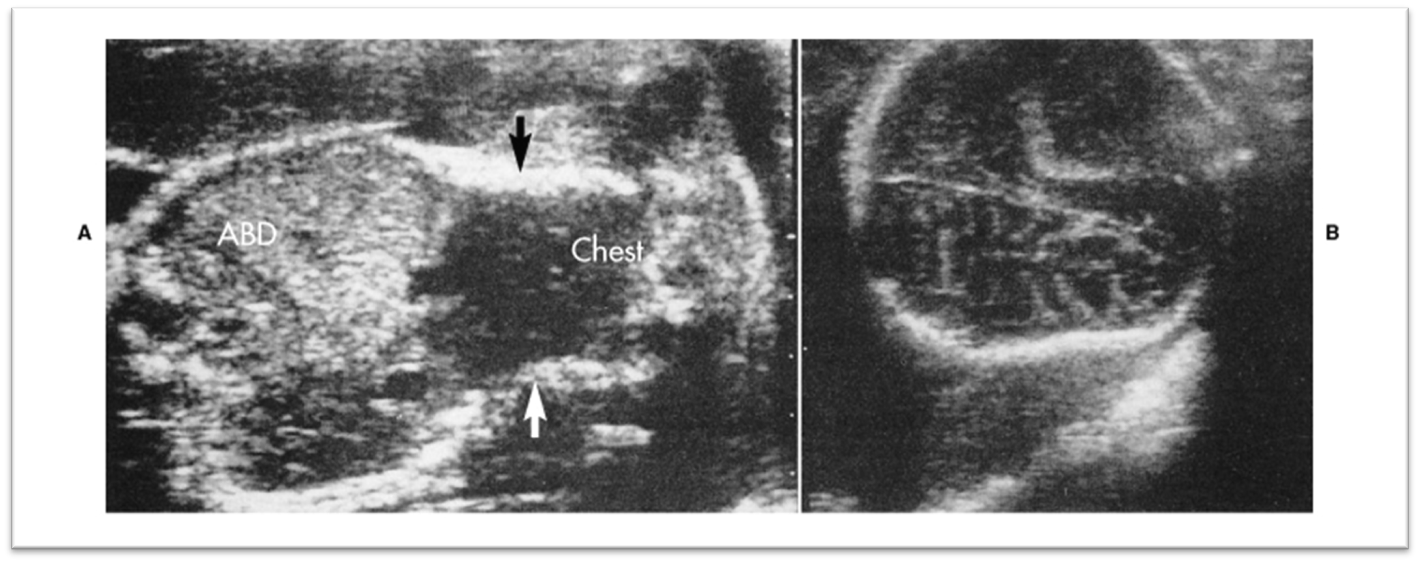

what is this image showing?

Osteogenesis Imperfecta

What are these images showing?